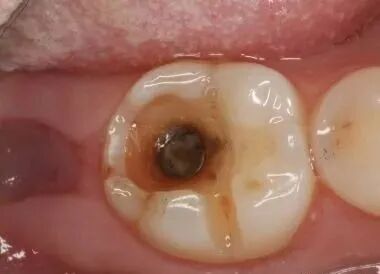

第三階段:牙齒超過一半爛掉,說明已經重度蛀牙,細菌傷及牙髓牙神經,還伴隨著劇烈疼痛,牙神經病變這時得根管治療處理,挽救傷痕累累的牙齒。

一是蛀牙出現疼痛,說明牙髓受細菌感染,可能已經引起牙髓炎,這時得進行根管治療;

三是蛀牙引起牙根發炎,牙龈上還會長膿包,醫生會拍片檢查症狀。